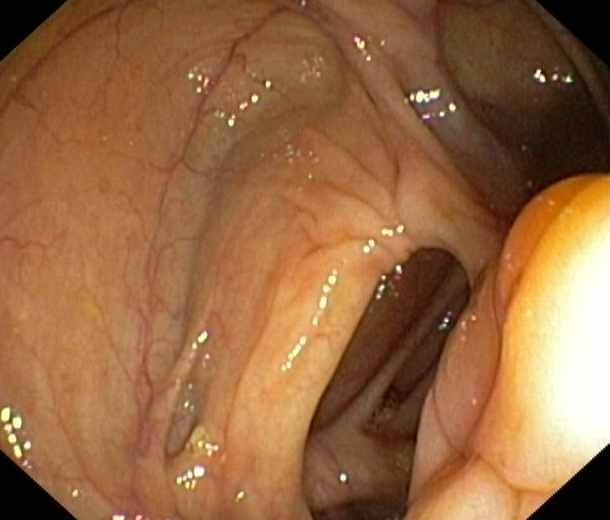

Ileocaecal valve